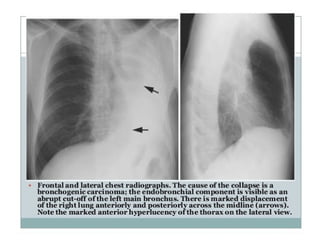

sign. a. Chest X-ray of a

patient with a centrally

located mass. The

reverse S sign due to

right upper lobe

atelectasis is clearly

depicted. The lateral

portion of the ‘S’ is

formed by the superiorly

displaced minor fissure

• Golden‘s (reverse S) sign.a. Chest X-ray of a patient with a centrally located mass. The reverse S sign due to right upper lobe atelectasis is clearly depicted. The lateral portion of the ‘S’ is formed by the superiorly displaced minor fissure and the medial portion by the mass (arrows). b. Golden S.